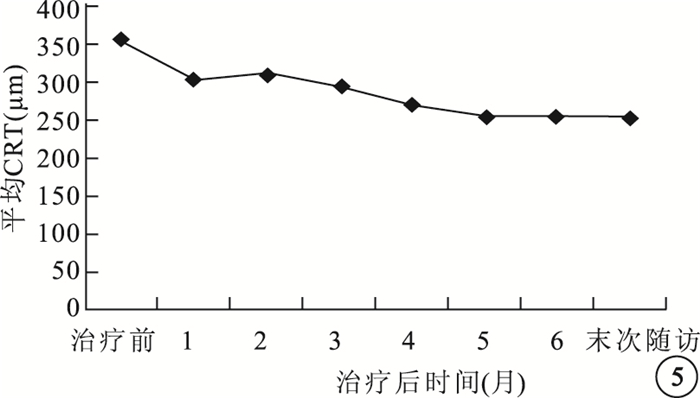

治療后1、3、6個月及末次隨訪時,患眼平均BCVA分別為(52.30±21.16)、(54.45±20.47)、(54.30±19.86)、(53.00±20.21)個字母,較治療前分別提高了(11.10±8.49)、(13.25±8.35)、(13.10±7.87)、(11.80±7.27)個字母,差異均有統計學意義(t=5.85、7.09、7.44、7.25,P<0.01)(圖 4)。治療后1個月視力顯著提高6只眼,占30%;提高8只眼,占40%;穩定6只眼,占30%;末次隨訪時,視力顯著提高6只眼,占30%;提高9只眼,占45%;穩定5只眼,占25%。

圖4

治療后不同時間患眼平均BCVA提高字母數比較

圖4

治療后不同時間患眼平均BCVA提高字母數比較

治療后1、3、6個月及末次隨訪時,患眼平均BCVA分別為(52.30±21.16)、(54.45±20.47)、(54.30±19.86)、(53.00±20.21)個字母,較治療前分別提高了(11.10±8.49)、(13.25±8.35)、(13.10±7.87)、(11.80±7.27)個字母,差異均有統計學意義(t=5.85、7.09、7.44、7.25,P<0.01)(圖 4)。治療后1個月視力顯著提高6只眼,占30%;提高8只眼,占40%;穩定6只眼,占30%;末次隨訪時,視力顯著提高6只眼,占30%;提高9只眼,占45%;穩定5只眼,占25%。

圖4

治療后不同時間患眼平均BCVA提高字母數比較

圖4

治療后不同時間患眼平均BCVA提高字母數比較